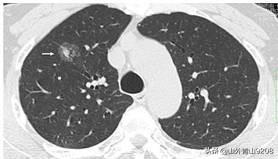

现在检查出肺内结节的人很多,你查出的是毛玻璃样结节,是相对特殊的一种肺内结节,因为跟肺腺癌相关性很高,因此要引起重视。

肺内毛玻璃样结节的分类?

1.纯毛玻璃样结节:

5mm以下的每年复查;

5mm以上的3个月、6个月复查一次,如果没变化后面每年复查。如果出现结节变大、结节内混杂成分增大多、血管进入则需手术处理。

1cm以上的也需手术处理

2.部分实性毛玻璃结节:需要手术治疗

大于8mm的磨玻璃结节,恶性比例高,建议手术治疗,手术一般可采用微创方式,早期患者术后无需化疗。

小于8mm的磨玻璃结节,如果有明显的毛刺征,或者表现为混合型的,建议手术治疗;

小于8mm的纯磨玻璃结节,如无明显恶性特征,建议积极随访。每三个月复查一次。一直复查三年。如果病灶实变或者变大,应该立刻手术。